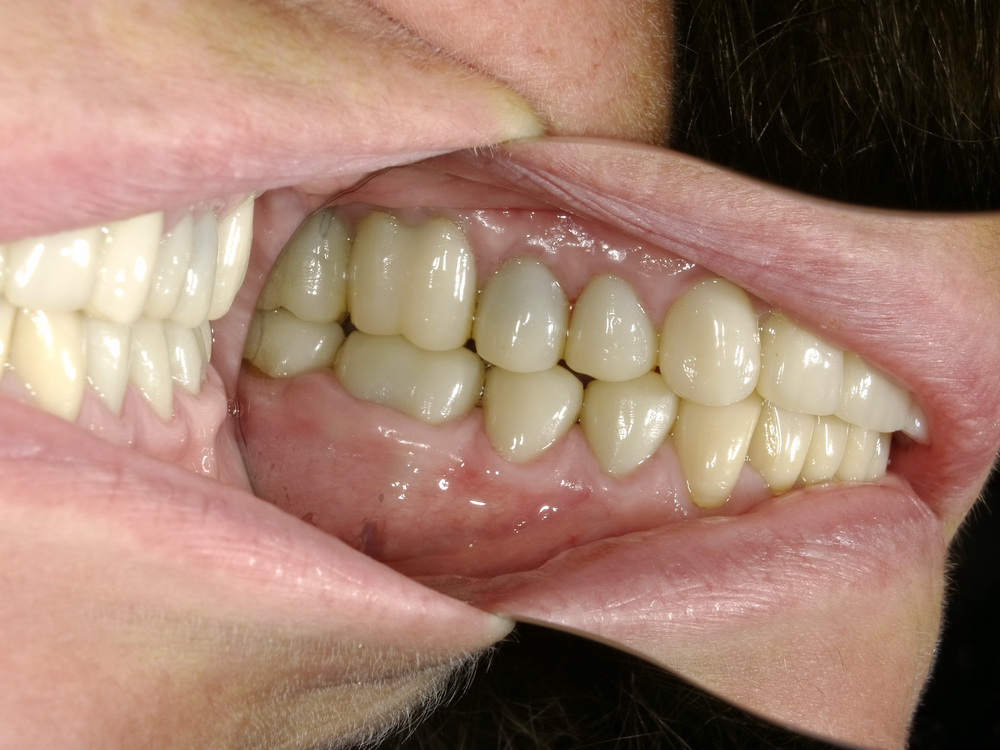

Nach mehreren Monaten Erprobungszeit der funktionstherapeutisch eingestellten Bisslage beginn nunmehr die Umsetzung der Versorgung mit Laborgfertigten Dauerprovisorien in eine Versorgung mit definitiven zahntechnischen Kronen.

Die neue Versorgung beginnt mit der Entfernung der Dauerprovisorien im Unterkieferseitenzahnbereich.